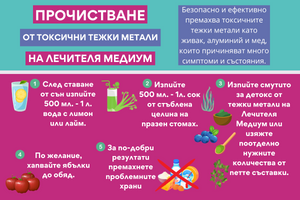

Прочистване от токсични тежки метали на Лечителя Медиум

от Aneliya Dikova • 4 мин. четенеПрочистването от токсични тежки метали от книгата на Антъни Уилям "Прочистване за здраве" премахва токсичните тежки метали като живак, алуминий и мед от мозъка и тялото. Тези метали причиняват или са частично отговорни за много симптоми и състояния, включително синдром на дефицит на вниманието и хиперактивност (ADHD), аутизъм, екзема, мигрена, мозъчна мъгла, проблеми с паметта, тревожност, депресия, биполярно разстройство и много други. -